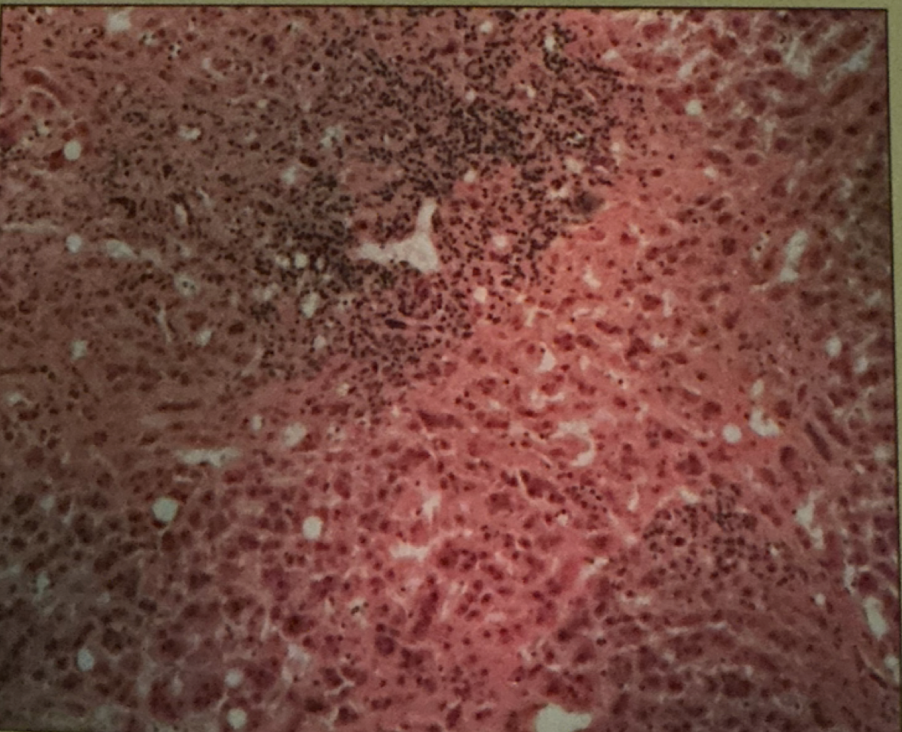

hodgkin’s granuloma

hodgkin’s granuloma

cancer of lymph system - breakdown of red and white pulp

reed-sternberg cells